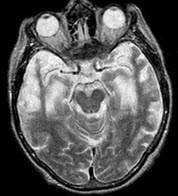

50、单项选择题

患者,女,70岁,有高血压和糖尿病史,左侧肢体活动不灵,突发外出迷路1天入院。MRI显示如图。

常见的病理改变不包括()

A.脑出血

B.脑梗死

C.脑萎缩

D.侧脑室扩张

E.血管平滑肌中层细胞嗜锇颗粒沉积

患者,50岁,高血压病史,反复出现TIA、腔隙性梗死,痴呆,MRI如图,下列哪项诊断可能最大()

A.血管性痴呆

B.路易体痴呆

C.Pick病

D.Alzheimer病

E.CJD